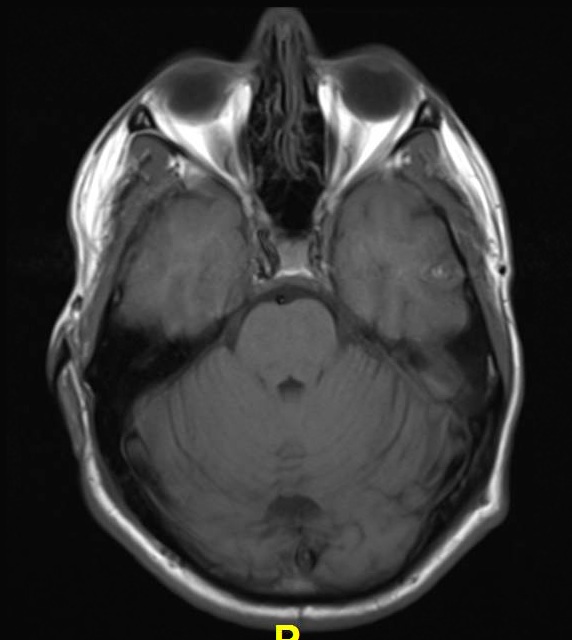

Lewy body dementia is typically diagnosed after other conditions are ruled out and the person's symptoms best fit with the diagnostic criteria for lbd. Related online courses on physioplus. Lewy body dementia stage 2 possibilities. Ct and mri show no characteristic changes in lewy body dementia but can initially help rule out other causes of dementia. Many people also experience changes in alertness including daytime sleepiness, confusion or staring spells. Read about the symptoms and what can help. Dementia with lewy bodies appears to be the second most common form of dementia, accounting for about one in five cases. Lewy body dementia, also known as dementia with lewy bodies, is the second most common type of progressive dementia after alzheimer's disease dementia.

Lewy, the scientist who discovered them. Loss of substantia nigra hyperintensity on 7 tesla mri of parkinson's disease, multiple system atrophy, and progressive supranuclear palsy. Besides nuclear imaging methods, the clinical utility of structural neuroimaging with magnetic resonance imaging (mri) for differential comparison between dementia with lewy bodies and alzheimer's disease. You also might see things that aren't there, called hallucinations. Lbd is a term that covers two conditions that have similar. Protein deposits, called lewy bodies, develop in nerve cells in the brain regions involved in thinking, memory and movement (motor control). Certain nuclear scans of the brain, including positron emission. How is lewy body dementia (ldb) diagnosed? Dr michael firbank discusses his study using functional mri in lewy body dementia and alzheimer's disease at the newcastle university institute. Focal atrophy in dementia with lewy bodies on mri: Memory loss is not always an early symptom. Lewy body dementia (lbd) is a type of progressive dementia. Many people also experience changes in alertness including daytime sleepiness, confusion or staring spells.

Lewy, the scientist who discovered them. These deposits, called lewy bodies, affect chemicals in the brain whose changes, in turn, can lead to problems with thinking, movement, behavior, and mood. Many people also experience changes in alertness including daytime sleepiness, confusion or staring spells. Mri can show loss of brain cells (atrophy), but this occurs with other types of dementia too. Lewy body dementia stage 2 possibilities.

By this point, most caregivers are worried that something is seriously wrong and seek medical attention. These deposits, called lewy bodies, affect chemicals in the brain whose changes, in turn, can lead to problems with thinking, movement, behavior, and mood. Many people also experience changes in alertness including daytime sleepiness, confusion or staring spells. In lbd, protein deposits build up in the brain. Lewy body dementia (lbd) is a type of progressive dementia that leads to a decline in thinking, reasoning and independent function because. Dementia with lewy bodies or lewy body dementia is dementia caused by the presence of lewy bodies in the brain. Lewy body dementia (lbd) is often regarded as the second most common dementia in older individuals after alzheimer disease,1,2 possibly sharing the. Memory loss is not always an early symptom. How is lewy body dementia (ldb) diagnosed? Lewy body dementia symptoms include recent loss of memory, difficulty concentrating or paying attention, misperceptions of space and time. The deposits are called lewy bodies and are named after friedrich h. Mri can show loss of brain cells (atrophy), but this occurs with other types of dementia too. Protein deposits, called lewy bodies, develop in nerve cells in the brain regions involved in thinking, memory and movement (motor control).